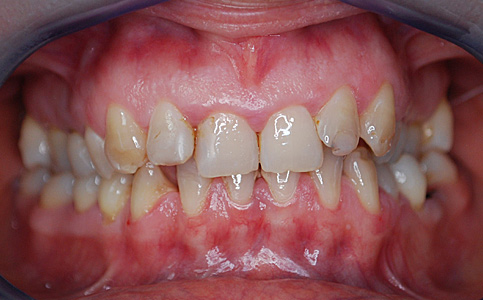

Dzięki koronom pełnoceramicznym w szczęce i żuchwie oraz uzupełnieniu braków zębowych implantami, pacjentka może znów się szeroko i pięknie uśmiechać.